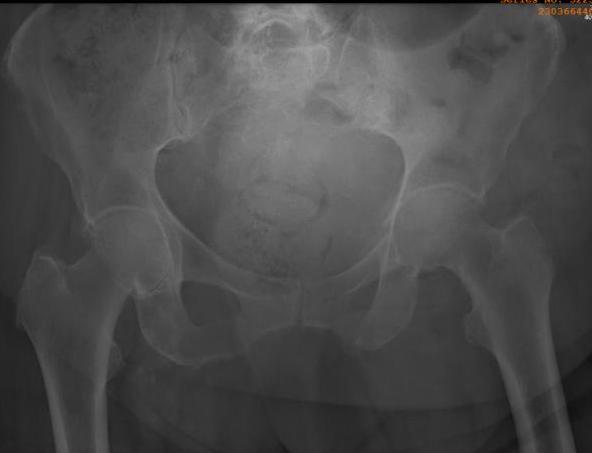

Fracture pattern

Lateral compression injury

- pubic rami fracture

- sacral alar fracture